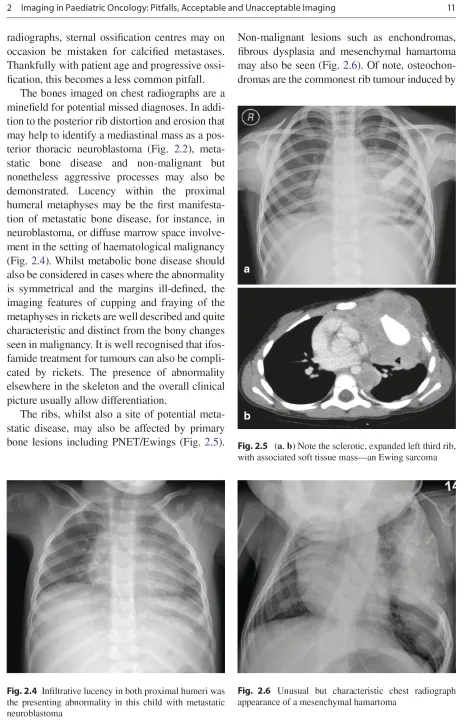

Sách Imaging in Pediatric Oncology (sách keo gáy, bìa mềm)

Year:2019

Edition:1st ed.

Language:english

Pages:402

This book, co-authored by an internationally acclaimed team of experts

in the field of pediatric oncologic imaging, provides a comprehensive

update on new advances in diagnostic imaging as they relate to pediatric

oncology. In contrast to other oncologic imaging texts focusing on the

radiology of specific tumors, this book emphasizes the important

fundamentals of imaging that every child with a new or treated

malignancy receives. Guidance is provided on the selection and use of

appropriate imaging techniques, with individual chapters devoted to each

of the major cross-sectional imaging modalities used in the detection

and follow-up of pediatric cancers, including PET-CT, PET-MRI,

whole-body MRI, and diffusion-weighted MRI. Additional nuclear medicine

techniques are addressed, and detailed attention is paid to more

advanced areas of practice such as contrast-enhanced ultrasound,

pediatric interventional radiology techniques, radiation treatment

planning, and radiation dose considerations (ALARA). Other areas covered

include screening of children with cancer predisposition syndromes,

treatment related complications, potential pitfalls during

neuro-oncologic imaging, and the risks and benefits inherent in

post-therapy surveillance imaging.